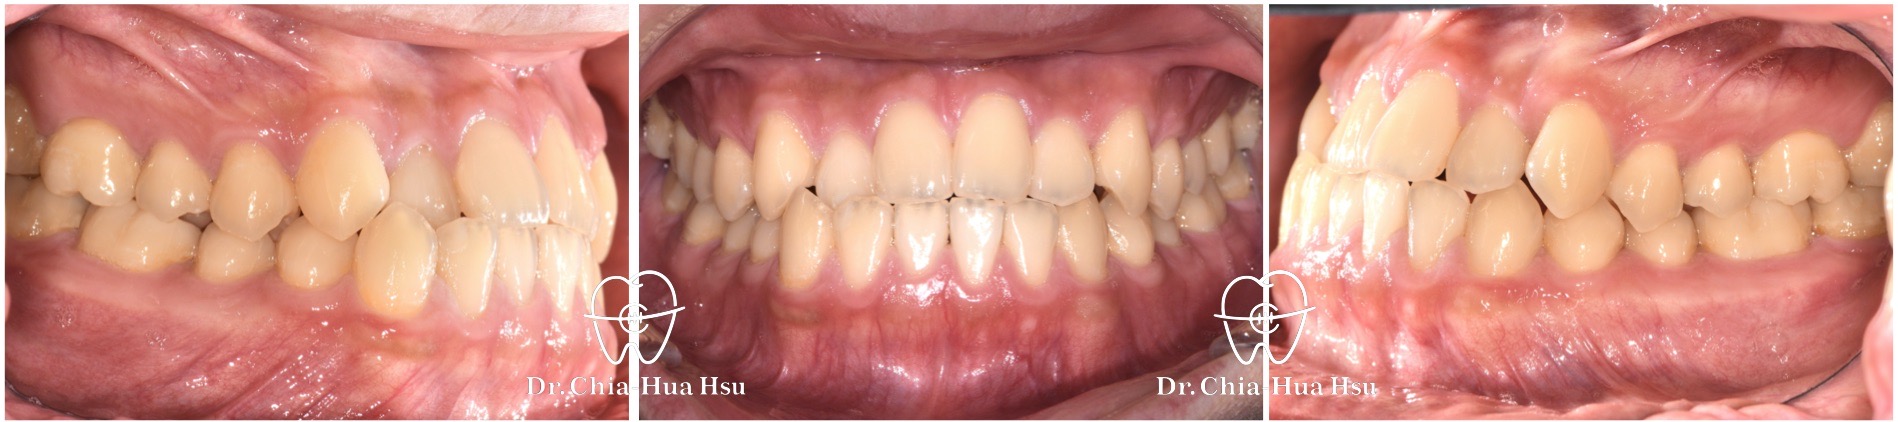

• 病患主訴:前牙錯咬、不整齊,有戽斗臉型,但不想做正顎手術。

• 問題分析:患者是輕微的骨骼三類咬合(Skeletal Class III)、下巴過長(戽斗)、前牙錯咬以及齒列不整齊。

• 治療方式:使用傳統金屬矯正器,並搭配垂直向橡皮筋牽引(Vertical elastics)使牙齒萌出。

• 治療時間:2 年。

• 治療結果:門牙露出增加、齒列排齊 ; 下臉部高度微增使下巴順時針微量旋轉,以修飾戽斗臉型。

治療前

治療後